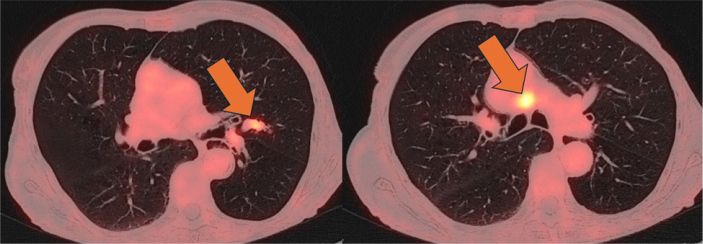

脑炎是一种具有传染性或自身免疫性的潜在威胁生命的疾病。自身免疫性脑炎包括与特异性肿瘤神经抗体(如抗- hu)相关的副肿瘤变异,通常与恶性肿瘤有关。1型单纯疱疹病毒(HSV-1)是导致成人感染的主要原因。区分这些病因是很有挑战性的。我们报告的情况下,一个88岁的妇女入院与混乱后跌倒。初步评估显示临床症状符合脑炎。在住院期间,目睹了癫痫发作。脑脊液(CSF)分析显示轻度多细胞症,但未检测到感染因子,脑成像未显示明显异常。在抗癫痫治疗的初步改善后,患者的认知功能障碍恶化。首次症状出现4周后再次进行脑脊液检查,结果显示细胞增多症更轻,但HSV-1阳性,磁共振成像显示双侧海马高信号。首次脑脊液样本回顾性分析显示高滴度抗hu抗体。正电子发射断层扫描-计算机断层扫描发现高代谢肺病变和主动脉旁淋巴结,活检证实小细胞肺癌的诊断。免疫抑制和肿瘤治疗导致短暂的改善,随后是进行性神经退化。支持性护理最终被优先考虑。该病例强调了脑炎的诊断挑战,特别是当自身免疫和感染性特征重叠时,诊断结果具有误导性。在没有典型的单纯疱疹病毒相关特征的情况下,检测到1型单纯疱疹病毒不应延误对脑炎其他病因的调查。副肿瘤脑炎的早期识别是至关重要的,因为神经系统症状可能先于潜在恶性肿瘤的诊断。学习要点:神经抗体,如抗hu抗体,是脑炎的一种未被充分认识的病因,当临床怀疑是自身免疫性脑炎时,应专门进行检测。检测抗hu抗体需要进行全面的恶性检查。脑脊液中单纯疱疹病毒1型聚合酶链反应阳性不能明确证实活动性感染,必须结合患者的临床表现进行解释。

Encephalitis is a potentially life-threatening condition with infectious or autoimmune aetiologies. Autoimmune encephalitis includes paraneoplastic variants associated with specific onconeural antibodies such as anti-Hu, frequently linked to malignancies. Herpes simplex virus type 1 (HSV-1) is the leading infectious cause in adults. Differentiating between these aetiologies can be challenging. We report the case of an 88-year-old woman admitted with confusion following a fall. Initial evaluation showed clinical signs consistent with encephalitis. During hospitalisation, a seizure was witnessed. Cerebrospinal fluid (CSF) analysis revealed mild pleocytosis, but no infectious agent was detected, and brain imaging revealed no significant abnormalities. After initial improvement under antiepileptic therapy, the patient experienced worsening cognitive dysfunction. Repeat CSF testing 4 weeks after initial symptom onset showed even milder pleocytosis but was positive for HSV-1 and magnetic resonance imaging showed bilateral hippocampal hyperintensities. Analysis of the first CSF sample retrospectively revealed high-titer anti-Hu antibodies. Positron emission tomography-computed tomography scan identified a hypermetabolic lung lesion and para-aortic lymph node, with biopsy confirming the diagnosis of small cell lung cancer. Immunosuppressive and oncologic treatment led to transient improvement, followed by progressive neurological deterioration. Supportive care was ultimately prioritized. This case underscores the diagnostic challenges of encephalitis, especially when autoimmune and infectious features overlap, and diagnostic findings are misleading. Detection of HSV-1 should not delay the investigation of alternative causes of encephalitis in the absence of typical HSV-related features. Early recognition of paraneoplastic encephalitis is critical, as neurologic symptoms may precede the diagnosis of underlying malignancy.